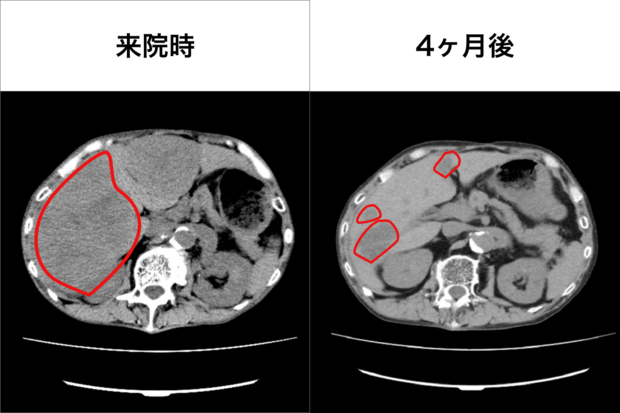

胃がん患者IさんのCT腹部画像(写真提供/船戸クリニック)

[写真 2/9枚目] 胃がん患者IさんのCT腹部画像(写真提供/船戸クリニック)